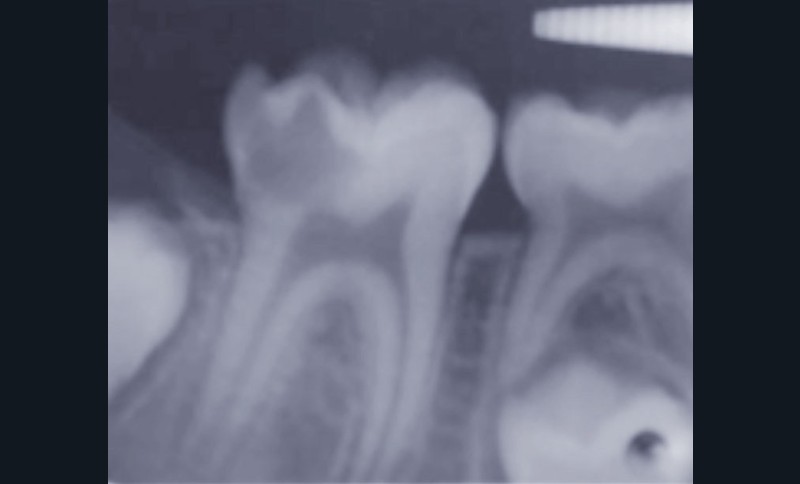

Restaurer sans tenon la dent dépulpée (fig. 4, 5, 6)

Selon les analyses de la littérature récente, la dent dépulpée n’est pas plus fragile que la dent pulpée. En revanche, les pertes de structure (a fortiori mésio-occluso-distale, lorsque les deux crêtes marginales sont perdues), et plus encore les tenons radiculaires, sont les éléments qui fragilisent la dent dépulpée. Ainsi, aussi souvent que possible, la dent dépulpée sera reconstituée sans tenon.

Lorsque la dent présente 4 parois résiduelles, une restauration en composite direct est indiquée. Pour 3 parois avec au moins une crête marginale, une restauration directe ou indirecte convient, si toutefois elles sont collées, car le collage augmente la résistance mécanique de l’organe dentaire résiduel. Pour 2 parois sans crêtes marginales, l’épaisseur des parois et la nature de la dent (les prémolaires étant plus fragiles que les molaires) vont permettre d’arbitrer entre reconstitution partielle collée ou endocouronne : le sertissage de la dent résiduelle ainsi obtenu la renforce considérablement. Le recours au tenon radiculaire sera donc réservé aux situations de délabrement très important, et il sera utilisé dans un but de rétention, et non pas dans un but de consolidation de l’organe dentaire.